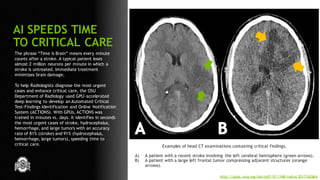

The phrase “Time is Brain” means every minute

counts after a stroke. A typical patient loses

almost 2 million neurons per minute in which a

stroke is untreated. Immediate treatment

minimizes brain damage.

To help Radiologists diagnose the most urgent

cases and enhance critical care, the OSU

Department of Radiology used GPU-accelerated

deep learning to develop an Automated Critical

Test-Findings Identification and Online Notification

System (ACTIONS). With GPUs, ACTIONS was

trained in minutes vs. days. It identifies in seconds

the most urgent cases of stroke, hydrocephalus,

hemorrhage, and large tumors with an accuracy

rate of 81% (stroke) and 91% (hydrocephalus,

hemorrhage, large tumors), speeding time to

critical care.

Examples of head CT examinations containing critical findings.

A) A patient with a recent stroke involving the left cerebral hemisphere (green arrows).

B) A patient with a large left frontal tumor compressing adjacent structures (orange

arrows).